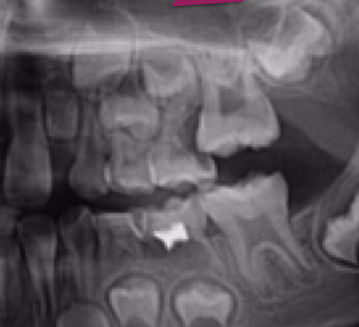

Vamos deixar isso mais claro…..clinicamente, o que se observa é a irrupção somente da porção distal do primeiro molar permanente. Vamos ver a imagem ao lado (Figura 01)…clinicamente é possível ver que a porção mesial está “escondida” pelo segundo molar decíduo.

Porém, apesar da característica clínica, o diagnóstico definitivo da impacção do primeiro molar permanente será realizado clinica e radiograficamente (Figura 02). O exame clínico é fundamental e indica um atraso na irrupção do primeiro molar permanente, porém o diagnóstico definitivo da impacção será determinado pelo exame radiográfico. E, portanto, diante das características clínicas e radiográficas iremos determinar a característica da impacção e a conduta terapêutica mais adequada.